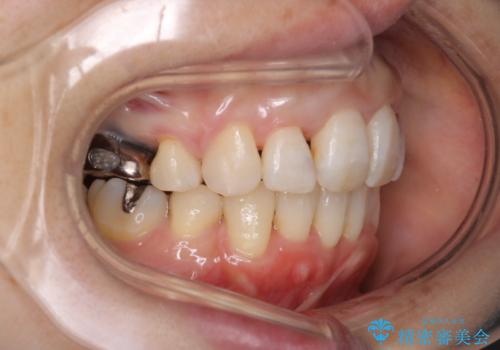

重度のガタガタと出っ歯をワイヤーによる抜歯矯正で整った歯並びへ

- 全体的ながたがたを主訴に来院されました。

上顎の前歯は前方に傾斜して、下顎の前歯は強いガタガタが見られました。

前から4番目の歯を上下左右合計2本抜歯して、歯並びを整える計画としました。

ワイヤー矯正にて治療しました。